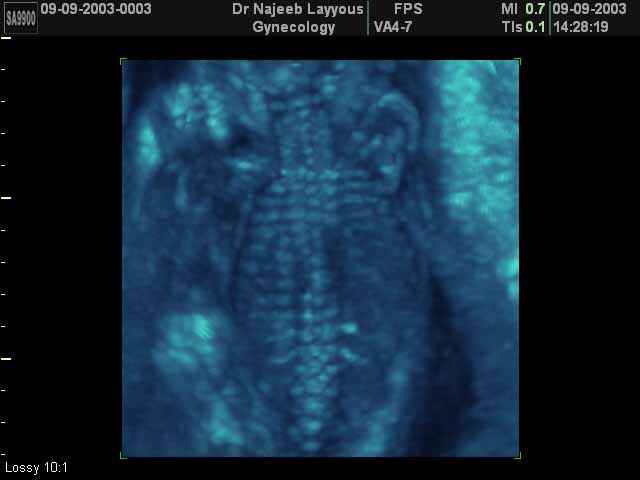

- Fetal Skeleton Ultrasound Photos